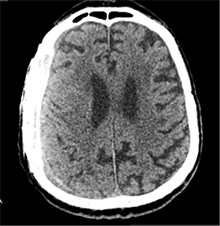

53 m. vyras sumuštas gatvėje ir greitosios medicinos pagalbos atvežtas į Priėmimo skyrių. Pacientui atlikta galvos kompiuterinė tomografija (GKT). Rasta: poūmė, stora, apie 16 mm dydžio subdurinė hematoma (SDH) dešinėje pusėje konveksitaliai ir ūmi nedidelė SDH kairėje pusėje frontoparietaliai. Vidurio struktūrų dislokacija (VSD) į kairę – minimali. Kairėje – kaukolės skliauto linijinis lūžis. Nustatyta nosies kaulų, nosies pertvaros, dešiniojo viršutinio žandikaulio kaktinės ataugos ir kūno, sinuso sienelių lūžių, dešinės akiduobės medialinio krašto lūžių ir dešiniojo skruostinio lanko lūžių (1 pav.). 2020 m. liepos mėn. pacientas skubos tvarka operuotas: atlikta dešinė kraniotomija, pašalinta hematoma. Atlikus kontrolinę GKT, buvo matyti, kad pašalinta didžioji hematomos dalis (2 pav.). Pacientas konsultuotas veido ir žandikaulio chirurgo, skubus chirurginis gydymas neindikuotas. Praėjus 3 savaitėms, pacientas, esant gerai funkcinei ir neurologinei būklei, tolesnio gydymo perkeltas į slaugos ligoninę, vėliau išleistas gydytis ambulatoriškai.

1 pav. Prieš pirmąją operaciją (poūmė, stambi, iki 16 mm SDH apie dešinįjį pusrutulį, ūmi nedidelė SDH kairėje F-P; VSD į kairę ~3 mm)

2 pav. Po pirmosios operacijos (didžioji hematomos dalis pašalinta, VSD be dislokacijos)